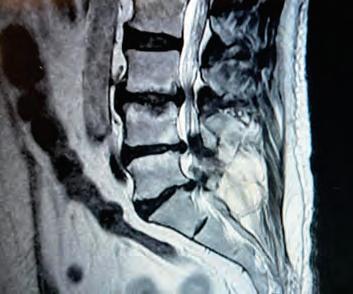

DR. LUISALBERTO RAMÍREZ LÓPEZ

Cirugía Neurológica, Cirugía Cerebrovascular, Cirugía de Columna Vertebral.

• MICROCIRUGÍA DE HERNIA DE DISCO

• CIRUGÍA DE HERNIA DISCAL CERVICAL

• DISCO ROTO

• CIÁTICA